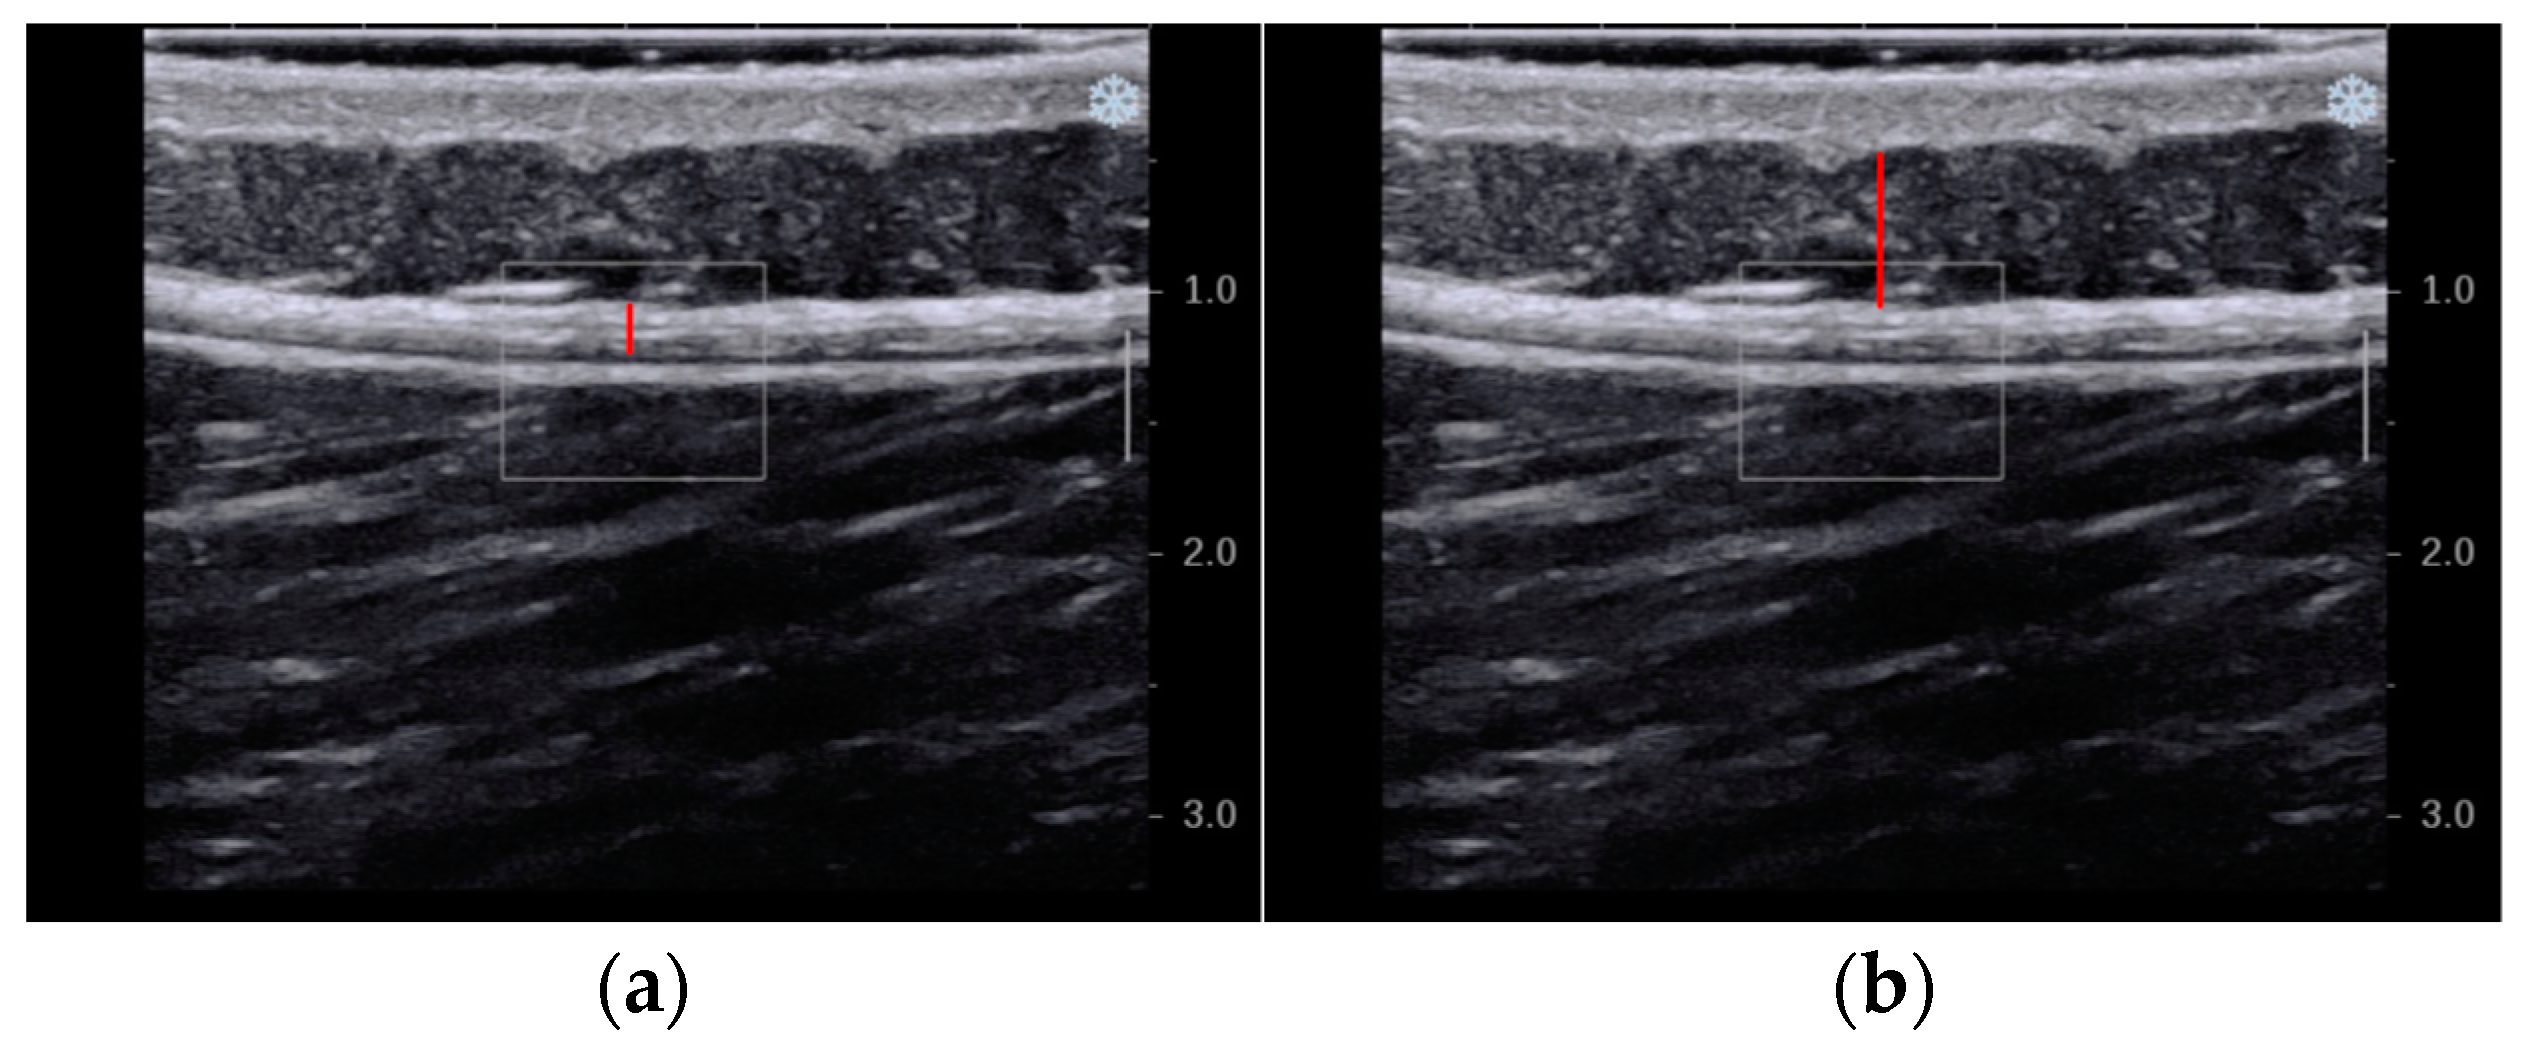

2.6.2. Secondary Outcome—Thickness